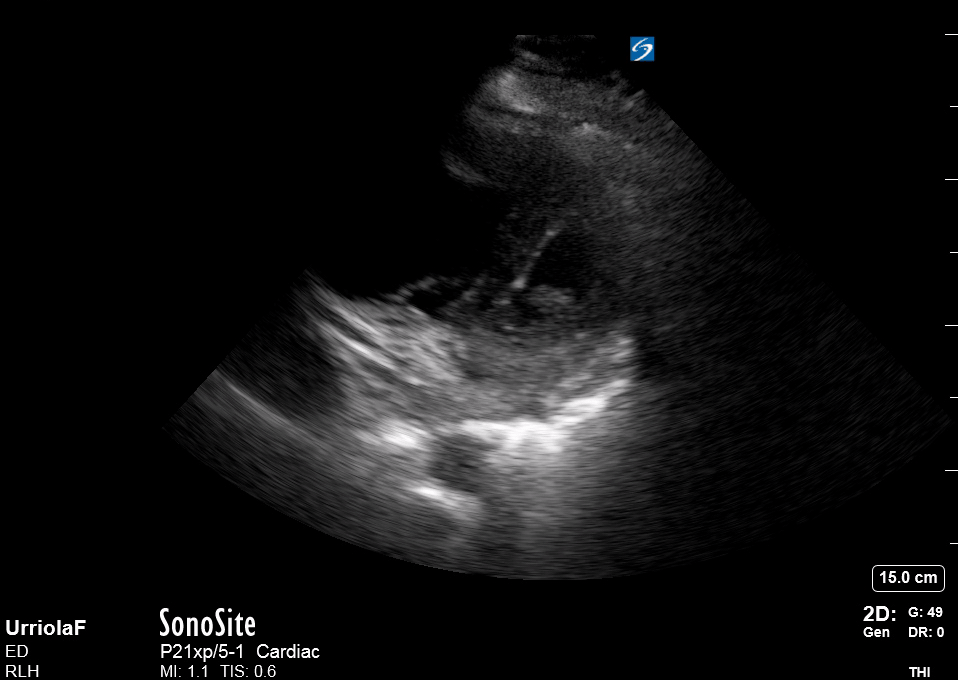

The PLAX view is versatile and allows the recognition of multiple landmarks, making it good for visual estimation of LV contractility. It is essential to optimize the view ensuring a true sagittal long axis, as being oblique to the LV chamber may underestimate its size and overestimate its emptying. The PSAX view at the level of the papillary muscles reveals the entire muscular circumference and concentric squeeze of the LV. It is useful to estimate both global function and focal wall motion abnormalities. The A4C view, although technically challenging, provides good insight into the global myocardial function and chamber size.

SIGNIFICANTLY IMPAIRED / DILATED LV

A severely depressed LV contractility, particularly when paired with a plethoric IVC or lung B-lines, indicates systolic heart failure. Chronically raised afterload can lead to severe dilation of the LV.

In contrast, hyperdynamic states are associated with decreased afterload and are classically found in patients with sepsis or severe hypovolaemia. A hyperdynamic heart should be accompanied by a small, collapsing IVC. Moreover, is essential to remember that tachycardic is not the same as hyperdynamic, as the latter is a measure of contractile activity and emptying. A tachycardic heart is not necessarily hyperdynamic.